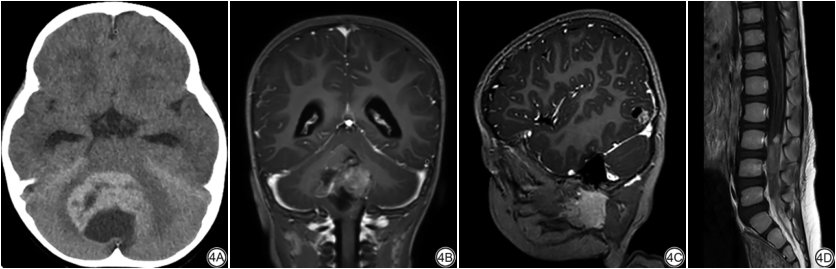

患儿中位年龄19个月,年龄范围5个月~39个月,原发灶位于幕下5例,幕上1例,幕上、幕下同时受累3例。瘤体最大径49.9±18.3 mm,伴有偏心囊变7例,瘤体出血6例,脑转移3例,脑、脊髓同时转移1例;瘤体实性成分在CT上以等或高密度为主,MRI T2WI信号混杂,DWI上瘤体实性成分呈高信号,ADC图为低信号,瘤体强化模式多样。

5例幕下肿瘤位于左桥臂1例,小脑蚓4例,其中1例小脑蚓肿瘤伴有右颞枕叶及脊髓转移;1例幕上肿瘤位于右额颞叶脑实质内;3例幕上幕下同时受累肿瘤:1例沿中脑导水管、第四脑室铸型生长并伴蛛网膜下腔、小脑半球多发转移结节,1例沿四叠体池和第三脑室生长同时伴有左侧脑室转移,1例位于第四脑室和第三脑室后部同时伴有左颞叶单发转移结节。9例肿瘤原发灶最大径30~90 (49.9±18.3) mm。

肿瘤实性为主7例、囊实性2例;8例有明确囊变,囊变分布于外周6例(图1B,2B,3B,4A)、分布于中央1例、弥漫分布小囊变1例;6例伴有瘤内出血(图1E,2B,3A),其中1例相应SWI幅值图表现为多发斑片状明显低信号(图1E);伴有脑转移3例,同时伴有脑、脊髓转移1例(图4C,4D);病变在T1WI上呈等信号3例,稍低信号1例(图2A),混杂信号5例(图1A,3A),T2WI上呈等信号3例,混杂信号6例(图1B,2B,3B);高b值DWI上,瘤体实性成分呈中等高信号2例,明显高信号7例(图1C,2C),9例ADC图均表现为明显低信号(图1D,2D,3C),对应平均ADC值(ADCmean)范围为(0.42~0.60)×10-3 mm2/s;伴有明显瘤周水肿1例(幕上脑实质病变),伴轻中度瘤周水肿5例,无明确瘤周水肿3例;伴有幕上脑室扩张6例,其中5例同时伴有不同程度室旁水肿;增强扫描肿瘤实性成分不均匀强化,其中轻中度强化4例(强化区域分布:沿实性区域弥漫分布2例,条片状分布1例,环形曲带样分布1例),明显强化5例[中央放射状分布1例(图3D),多结节堆积状分布2例,环形曲带样分布2例(图1F,2E)]。

既往通常认为AT/RT缺乏特异性影像学表现,随着对其认识不断加深,AT/RT具有一些相对特异性的影像表现,可能有助于提高其诊断率。AT/RT发病部位无特异性,可以发生在中枢神经系统的任何位置,多呈局灶性发病,表现为幕上或幕下肿块,也可以同时累及幕上、幕下,与本组部分病例肿瘤跨越幕上、幕下生长相似[7]。AT/RT肿瘤体积通常较大,本组病例瘤体最大径约30.0 mm~90.0 mm,首次就诊时瘤体最大径均在30 mm以上。有学者认为偏心分布囊变是AT/RT较为特征性的影像表现[16,17],亦有学者通过比较分析AT/RT和髓母细胞瘤中囊变的分布特点,证实前者囊变偏心分布更常见[18],本组有明确囊变病例中,偏心分布7例(7/8),与文献报道AT/RT易发生偏心囊变相符。本组病例伴有出血6例(6/9),与文献报道AT/RT容易发生出血坏死,约45%~63%患儿可见瘤体出血相符[7,16]。值得一提的是本组一名17个月龄男患儿初次就医时(主诉:颅缝狭窄)头颅CT未见明确占位性病变,7月后再次就诊(嗜睡、左侧肢体无力)行头颅MR平扫+增强发现右额颞叶巨大囊实性占位性病变,短短半年时间肿瘤迅速生长最大径达9.0 cm,说明该肿瘤细胞增殖活跃,与此类肿瘤Ki-67较高相符。AT/RT肿瘤细胞密集、核质比高,高b值DWI上肿瘤内水分子扩散受限明显加重呈高信号,对应ADC呈明显低信号。多项研究显示中枢神经系统AT/RT的ADC图表现为明显低信号,其ADC值范围约(0.45~0.85)×10-3 mm2/s,本组9例患儿范围(0.42~0.60)×10-3 mm2/s [ADCmean为(0.51±0.06)×10-3 mm2/s],与文献报道一致性较高[7,19,20]。文献报道曲带样环形强化在AT/RT中具有特异性,亦有学者称之为“盘山公路征”[16],我们的病例中有2例(2/8)表现为曲带样强化,与文献报道类似。此外,我们的病例中还可见其他多种强化方式,相似表现为肿瘤整体不均匀轻中度或明显强化,但强化模式多样,如中央放射状强化、多结节堆积样强化、局部条片样强化等。AT/RT易随脑脊液循环播散转移至脑内其他部位或脊髓,部分患儿初就诊时常伴有脑脊液播散灶[21],本组病例首次就诊时1例同时伴有脑组织、脊髓转移,3例伴有脑转移(脑实质转移1例,脑室转移1例,脑实质和蛛网膜转移1例)。Nowak等通过对43名已知分子亚型AT/RT进行影像学对比分析发现:ATRT-MYC亚型较其他两种亚型有更显著的瘤周水肿,而ATRT-SHH和ATRT-TYR亚型偏心囊变更见,ATRT-TYR和ATRT-MYC亚型有明显强化趋势而约三分之一ATRT-SHH亚型增强后无确切强化[22]。本组回顾性病例患儿未作相应基因型检测,无法与该文研究结果进行对比,以后的工作中对ATRT基因分型的应用有助于我们更深层次地认识AT/RT。